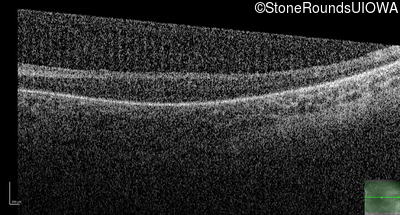

Optical Coherence Tomography - Right - No Light Perception

Exemplar / OCT Stack